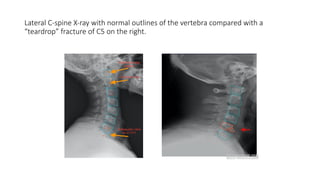

Lateral C-spine X-ray with normal outlines of the vertebra compared with a

“teardrop” fracture of C5 on the right.